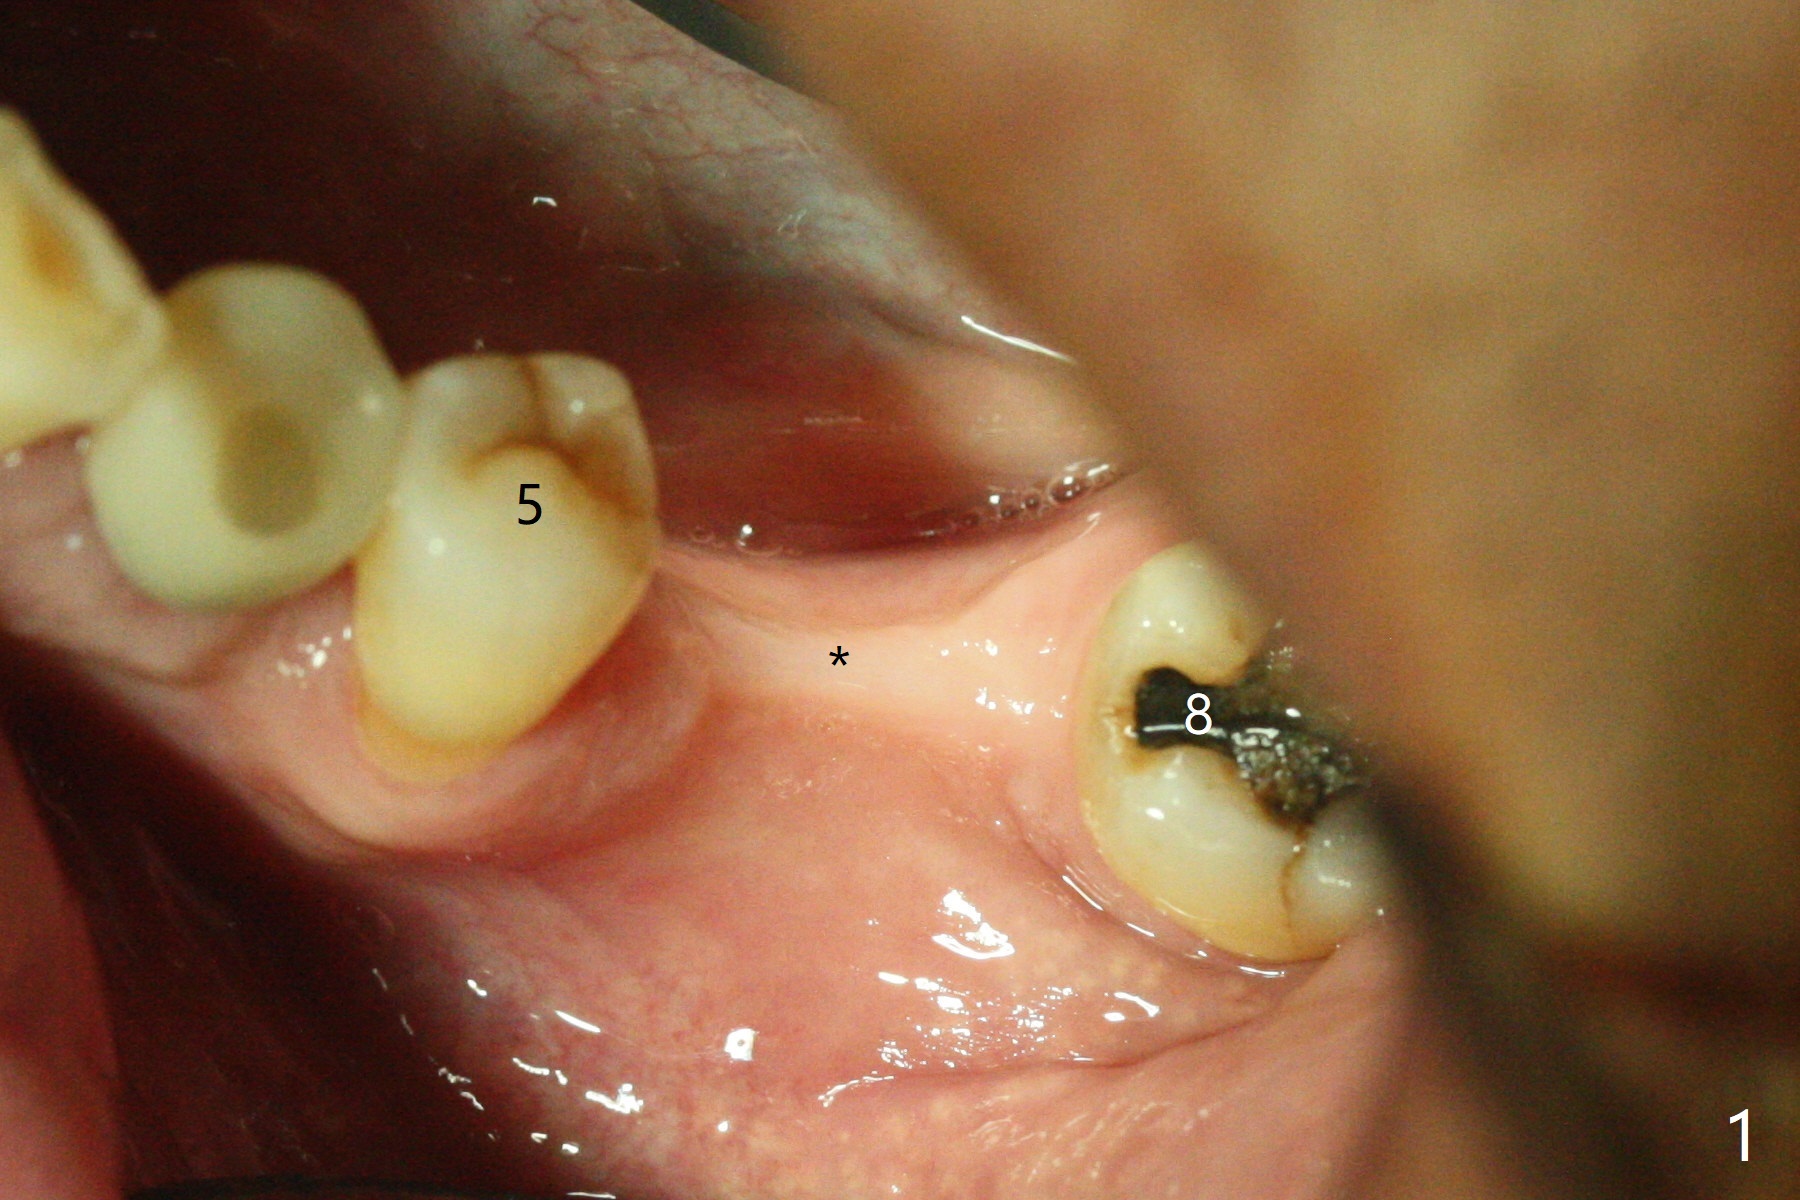

左下6,7导板设计种植两个小植体,牙槽嵴角化龈狭窄(图一:*),切开,钻洞,6处骨质密度高,钻头与植体直径必须一样,但是为了保证稳定性,最后1.5毫米钻头小0.5毫米,植体最后1-2毫米必须倒旋一次才能控制扭力不超过40Ncm,术后即刻根尖片显示4,6根尖部(密度2200单位,图二)螺纹弯曲(<),而7(密度670单位)钻头比植体小0.5毫米,植入扭力也大约40Ncm,不过螺纹没有变形。祸不单行,6植体冠部舌侧螺纹暴露约1毫米,放入自体骨后,盖膜(6个月),4-0铬羊肠线减张缝合(图三),牙槽嵴好像增宽了。术后两周伤口愈合(图四)。术后4.5个月切开暴露,尽管需要外科钻头去除植体冠部骨质,6舌侧植体螺纹仍暴露,放置4.5x3毫米愈合基台,7放置4x4(3)毫米修复基台(图五),但是接近8牙冠,无法修复,必须做局部牙齿矫正。术后7个月7放置3.4x3毫米愈合帽,6放置4.5x5.7(4)毫米修复基台,手拧紧,做临时牙冠,垫高,开始矫正;一个月后基台松动,扳手拧紧(30Ncm);7处3.4x3毫米愈合帽没有就位,由于远中牙槽嵴阻挡(图六:<)。